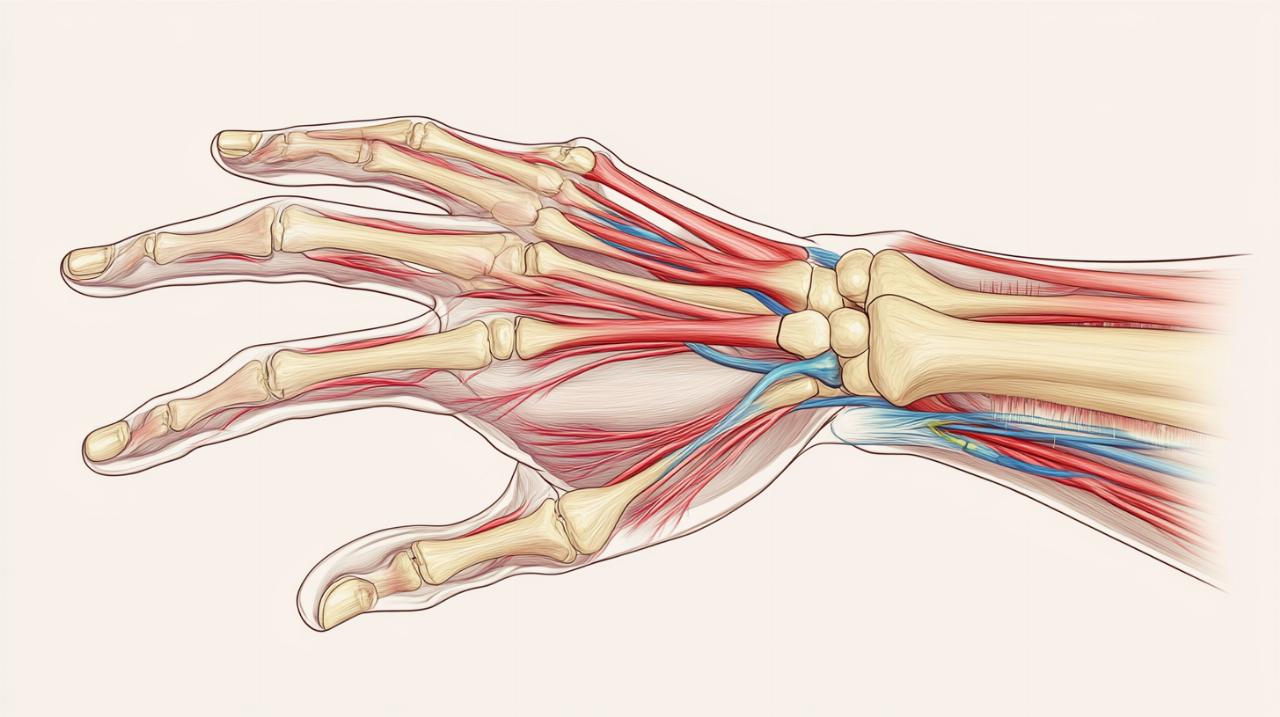

La déformation en boutonnière survient lorsque le tendon extenseur, plus précisément la bandelette centrale de l'extenseur, subit une rupture tendineuse au niveau de l'articulation interphalangienne proximale. Cette lésion provoque un déséquilibre biomécanique qui entraîne progressivement une posture anormale du doigt. L'articulation interphalangienne proximale adopte une position en flexion tandis que l'articulation interphalangienne distale bascule en hyperextension, créant ainsi l'apparence caractéristique qui donne son nom à cette pathologie.

Le diagnostic précoce constitue un élément essentiel pour garantir l'efficacité du traitement. Cliniquement, la déformation en boutonnière se manifeste par une impossibilité d'extension active de l'articulation interphalangienne proximale, alors que l'extension passive reste possible. Cette distinction permet de différencier la rupture tendineuse d'une raideur articulaire mécanique. Le patient présente typiquement un doigt dont l'articulation centrale reste fléchie malgré les efforts pour l'étendre, tandis que le bout du doigt adopte une position anormalement redressée.

L'examen physique réalisé par un spécialiste en chirurgie main permet généralement d'établir le diagnostic clinique. Néanmoins, l'imagerie joue un rôle complémentaire important. La radiographie aide à identifier une éventuelle fracture ou un arrachement osseux associé à la lésion tendineuse. L'échographie peut visualiser directement la rupture du tendon extenseur et évaluer l'étendue des dégâts. Ces examens s'avèrent particulièrement utiles lorsqu'une intervention chirurgicale est envisagée, permettant de planifier précisément le geste technique nécessaire à la réparation.